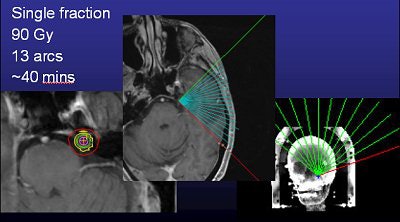

![]() |

| An example of a treatment plan for TN using a single isocenter to deliver a single fraction of 80 Gy to the TN nerve root. A single 5-mm collimator and a multiarc technique would be used to minimize dose to the brain stem. Image courtesy of Varian Medical Systems, Palo Alto, CA. |

These days, planning is done often with CT or MRI, with the latter used for planning and the former for treatment simulation. On the most basic level, all radiosurgery systems deliver high doses of ionizing radiation (65-90 Gy) to small intracranial targets via imaging guidance.

Murphy's list of linac shortcomings is, well, short. "I trained on (gamma knife). To train on a (Trilogy) system that was frameless and not proven was a hard thing to do. The dose is really high (90 Gy, four times the regular radiotherapy dose, but the same as gamma knife), and it's right next to the brain stem, so if you miss or the patient moves, you're going to fry the brain stem," he said.